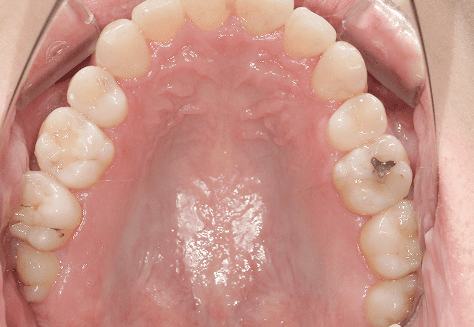

M.H

治療前

治療後

主訴

前歯が出ている。下の歯並びが特に気になる。奥歯でしっかり噛めない。

診断

上顎前突・叢生・シザーズバイト

年齢/性別

20代/男性

抜歯部位

下顎両側大三大臼歯(口腔外科にて)

上顎両側第一小臼歯・下顎左側側切歯

(当院にて5,500円×3) -

使用装置

上下エッジワイズ→インビザライン(PBM使用)

保定装置

上下ビベラリテーナー

料金

初回資料採得・・・・・・・30,000円

診断料・・・・・・・・・・33,000円

動的治療終了時資料採得・・5,500円 -

基本料金

880,000円

診察料金

5,500円×44回

治療期間

3年6カ月